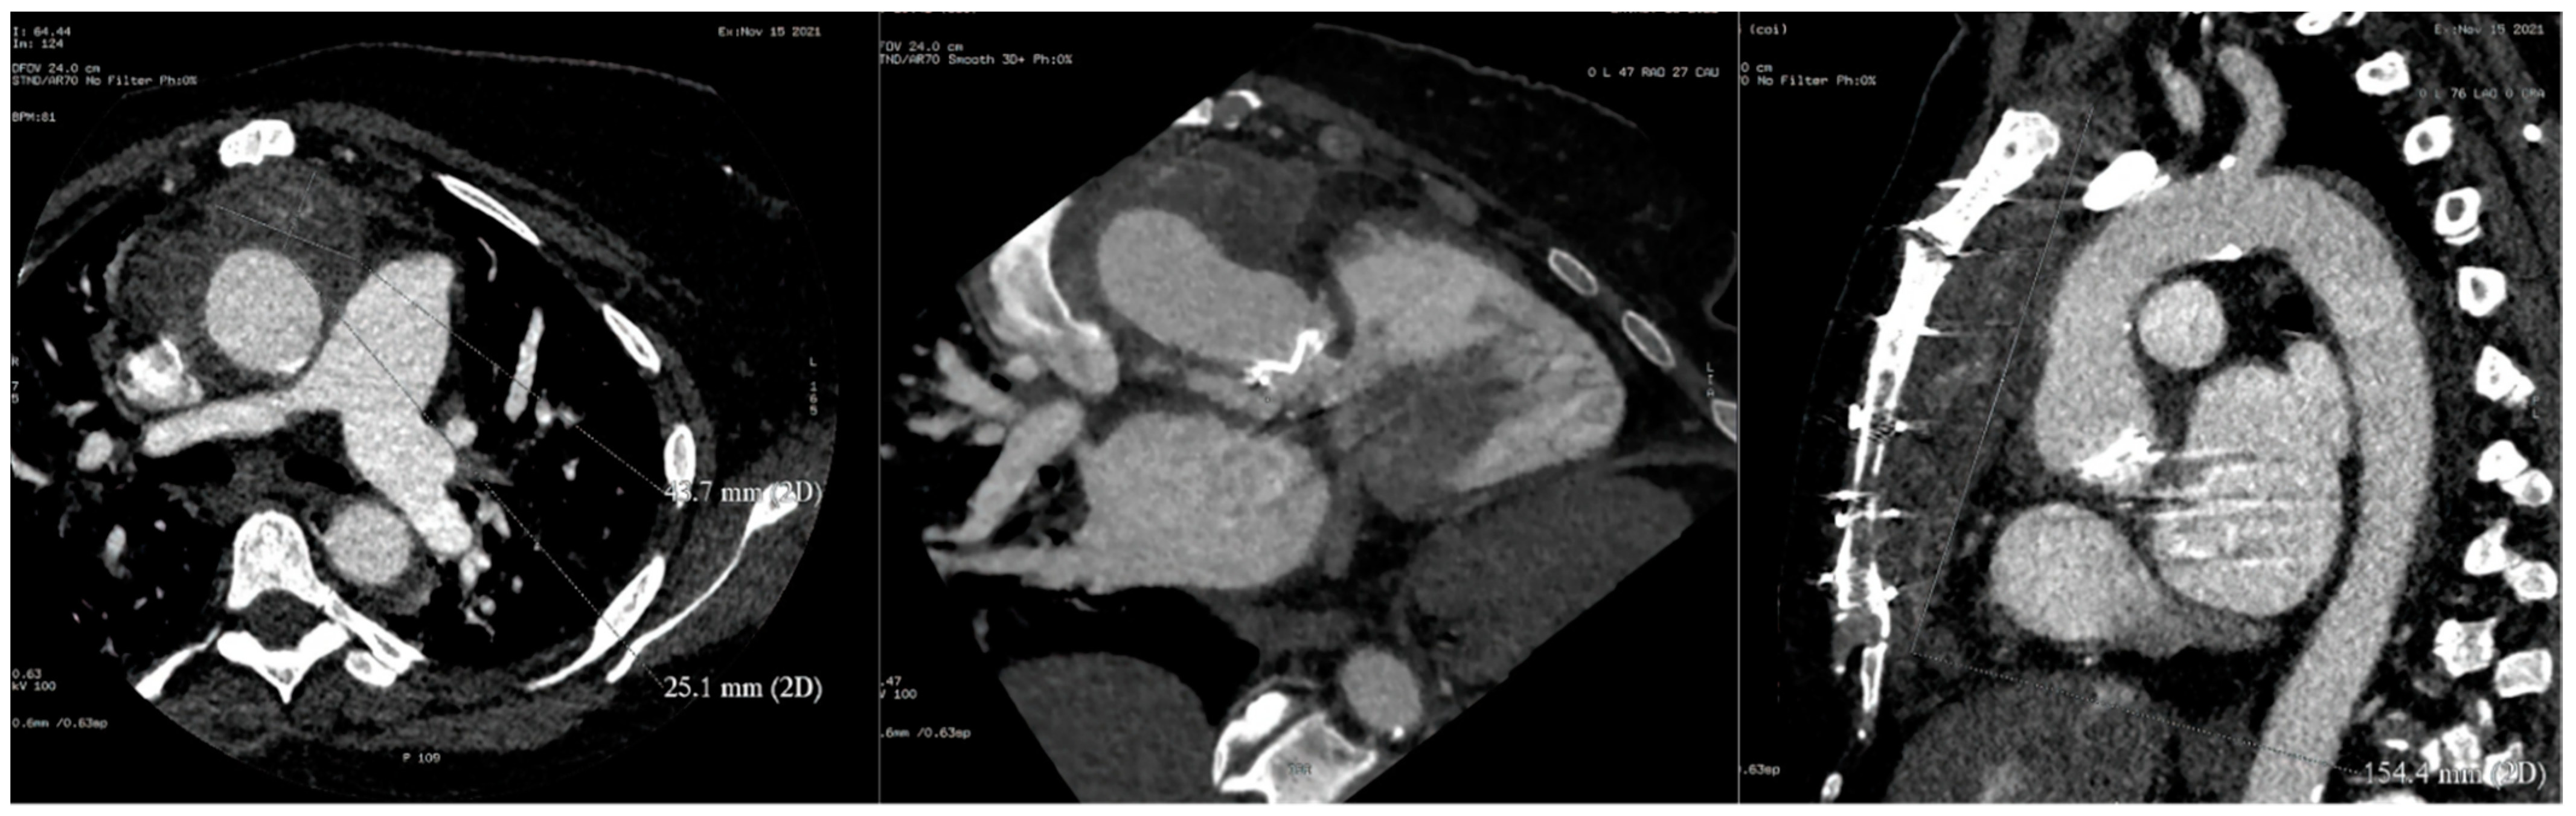

Refractory Salmonella Prosthetic Valve Endocarditis Complicated by Splenic Infarction and Aortic Pseudoaneurysm in a Patient with Double Prosthetic Valves: A Case Report

2. Case Presentation